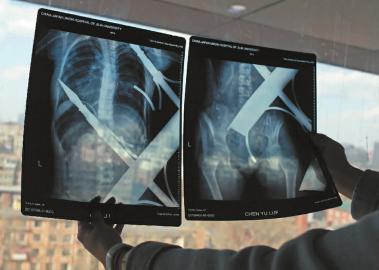

X光片顯示一根鋼筋將小女孩的右側(cè)肩膀刺穿,另外一根則從后背腰部以上靠近脊椎的地方穿入 新文化記者 白石 攝 成功把鋼筋破拆后,小雨立即被送往了手術(shù)室,接到指令后的20多分鐘里,消防戰(zhàn)士們一直在跟死亡競(jìng)速。

X光片顯示一根鋼筋將小女孩的右側(cè)肩膀刺穿,另外一根則從后背腰部以上靠近脊椎的地方穿入 白石 攝

在急診室的病床上,李紅旭看到了小雨?!八龗熘跗?,意識(shí)比較清醒?!边M(jìn)一步觀察,李紅旭一時(shí)說(shuō)不出話來(lái)———一根鋼筋穿透小雨右側(cè)肩膀,另一根則從后背腰部以上靠近脊椎的地方穿入,從小雨左肩部分穿了出來(lái)。兩根鋼筋由兩根角鐵連接,距離事發(fā),小雨背著這片鐵柵欄已經(jīng)近7個(gè)小時(shí)了。